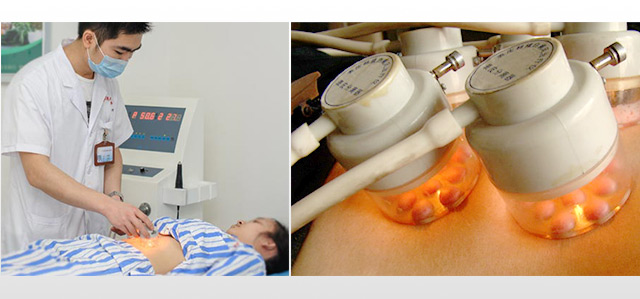

在“黑素细胞介入”过程中,“母细胞提取”与“磨皮”是决定手术是否成功的关键所在。“黑素母细胞提取”需要从皮肤基底层提取,保证黑素母细胞是最为完整、活跃度最好。“磨皮”是关系到黑色素成活的又一关键,磨皮太浅,成活率低,效果不好,而磨皮太深就会对真皮层造成伤害,会给皮肤留下疤痕。因此,“黑色素细胞种植术”不仅需要配备先进设备,还需医生的治疗技术水平过硬。

30余年专业医生亲自操刀取皮、磨削、植入,每个环节精细化操作,黑素母细胞成活率可达98.5%,复色均匀,不破坏真皮层,术后无瘢痕。

20分钟培养黑素母细胞,2小时内白斑区黑素细胞(黑素母细胞和黑色素细胞统称)成活,7天见效,约19天有黑色素生成,28天白斑颜色加深,逐步恢复。